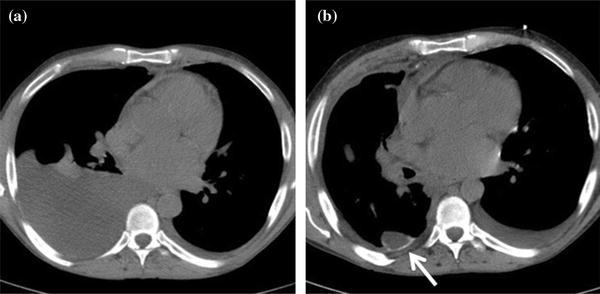

Các hình thức đáp ứng điều trị sớm của thuốc...

Khám phá các hình thức đáp ứng điều trị sớm với thuốc đích trong ung thư phổi giai đoạn 4: lâm sàng, hình ảnh, ctDNA, mô học và sinh học phân tử....